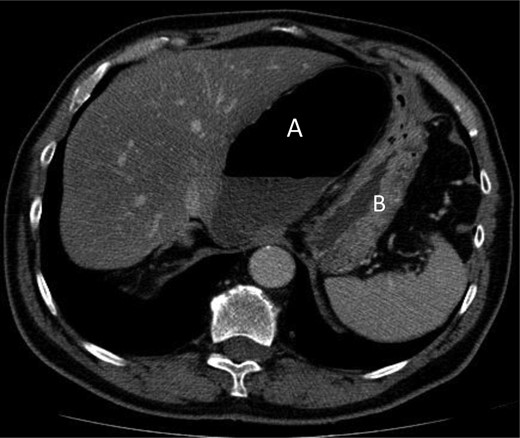

A 69-year-old patient presented to our emergency room with progressive dull abdominal pain and distension without nausea, vomiting or change in bowel habits. Physical examination showed pain with moderate guarding in the right upper and lower quadrants. A plain abdominal X-ray and a CT scan were performed. Radiological findings suggested the diagnosis of an internal hernia through the epiploic foramen and containing the right colon with important distension of the caecum (Fig. 1). Surgical exploration was then performed using an open approach. At laparotomy, we found an internal herniation of the caecum and the entire ascending colon through the foramen of Winslow (Figs 2 and 3). After hernia reduction, multiple patchy areas of caecal necrosis were observed (Fig. 4). A formal right hemi-colectomy was therefore performed. The postoperative recovery was uneventful.

The herniated segment after reduction, with areas of necrosis.